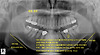

상하악후퇴-->교정-->여전히 상하악후퇴-->어긋난 어금니-->사이 충치 (21세) 작성자 김동오 작성시간 25.11.06 조회수 47